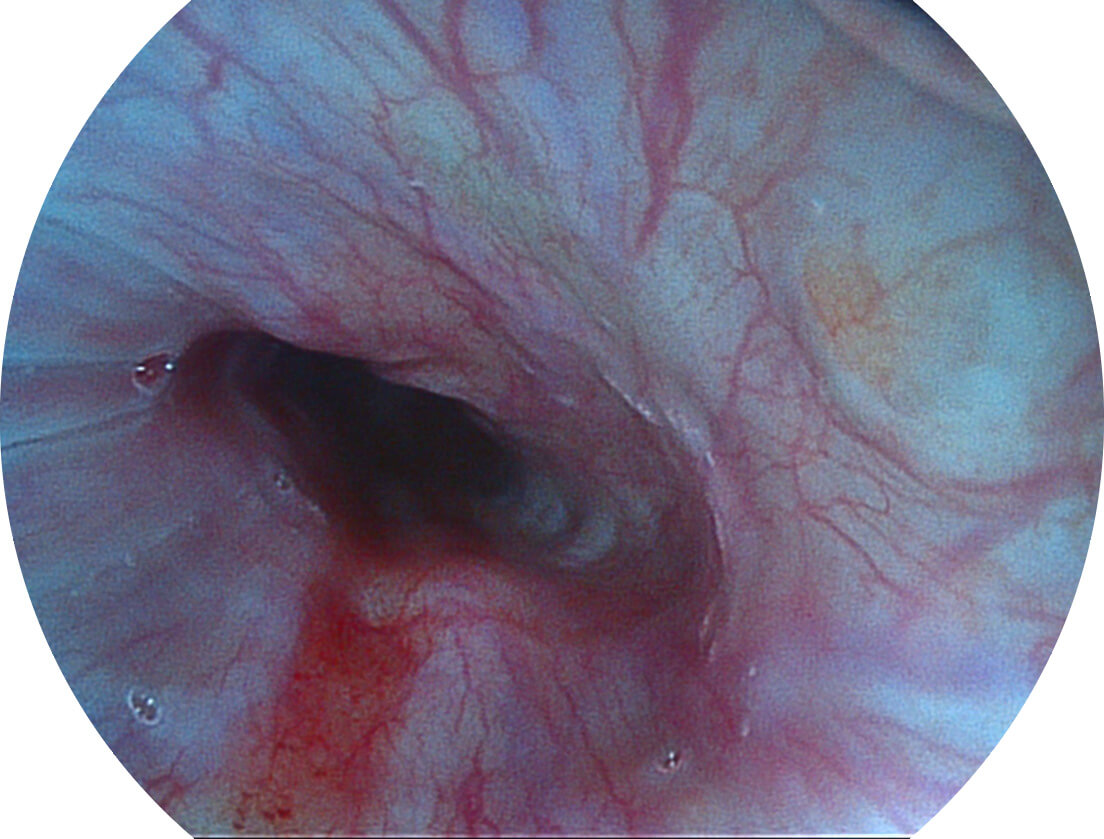

图像具有高亮度、高黏膜血管颜色对比度的特点,且不改变粘液、食物残渣、粪便的基本颜色,可在中远景下进行观察,助力消化道早期疾病的诊断。

• 白光图像 SFI图像

• 白光图像 VIST图像